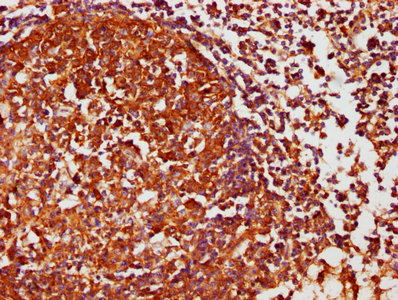

IHC image of CSB-PA006067LA01HU diluted at 1:1000 and staining in paraffin-embedded human lymph node tissue performed on a Leica BondTM system. After dewaxing and hydration, antigen retrieval was mediated by high pressure in a citrate buffer (pH 6.0). Section was blocked with 10% normal goat serum 30min at RT. Then primary antibody (1% BSA) was incubated at 4°C overnight. The primary is detected by a biotinylated secondary antibody and visualized using an HRP conjugated SP system.